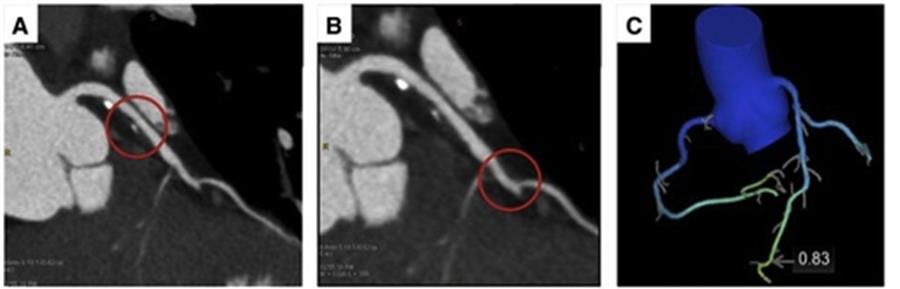

(A) Paziente di 59 anni sintomatico per angina atipica con anamnesi familiare di CAD, ipertensione, fumo, e probabilità pre-test intermedia di CAD con ECG da sforzo positivo. La ricostruzione multiplanare CCTA della coronaria anteriore sinistra discendente mostra un 45% (A, cerchio) e un 55% di stenosi, coinvolgendo l’origine del primo ramo diagonale (B, cerchio) con FFRCT di 0,83 (C).1